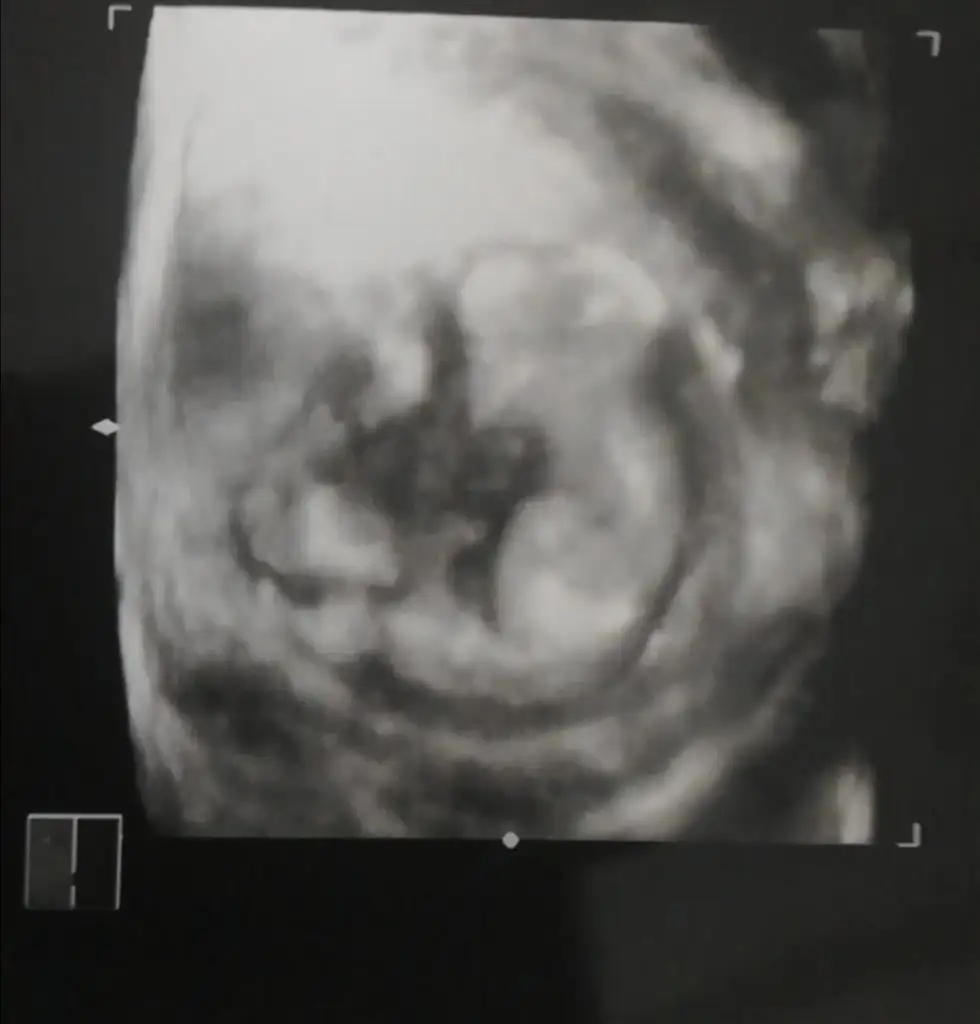

Eki Görüntüle 473829 bu bir erkek bebek genital nub cikintisi gayet yukarda

Eki Görüntüle 473837 bu benim kizim cikinti gayet net ve ortada ve ben kizim diyooo